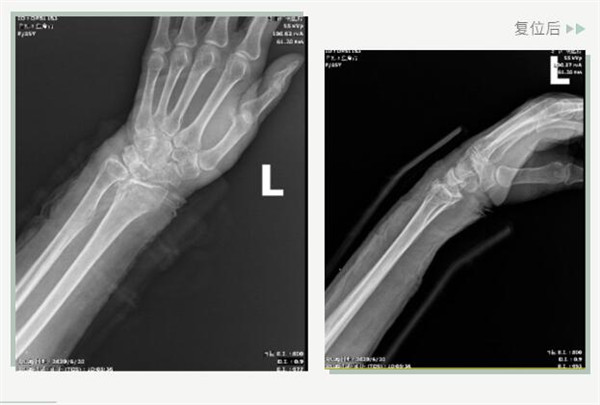

25日當(dāng)天,莊阿婆來(lái)到危立軍副院長(zhǎng)門(mén)診,經(jīng)拍片顯示,莊阿婆左橈骨遠(yuǎn)端粉碎性骨折,左髂骨至髖臼后緣及恥骨下支骨折??紤]到莊阿婆年紀(jì)較大,基礎(chǔ)病較多,難以經(jīng)受手術(shù)創(chuàng)傷,傳統(tǒng)手法復(fù)位更為合適。推、拽、按、捺……經(jīng)過(guò)危立軍副院長(zhǎng)一番手法復(fù)位后,再次拍片顯示莊阿婆橈骨遠(yuǎn)端骨折端復(fù)位位置良好,莊阿婆及其家人感到非常滿意。

復(fù)位后